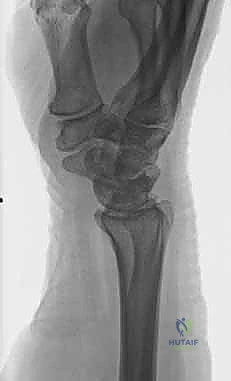

2. كسور رأس الزند (Ulnar Head Fractures)

رأس الزند هو الجزء المفصلي الدائري الذي يدور حوله الكعبرة.

* كسور مفصلية (Articular Fractures): تمتد خطوط الكسر لتشمل الغضروف المفصلي. إذا لم يتم إعادة العظام إلى وضعها التشريحي المثالي (Anatomic Reduction)، فإن المريض سيكون عرضة للإصابة بخشونة المفاصل المبكرة (Post-traumatic Osteoarthritis) وفقدان القدرة على تدوير الساعد.

* كسور غير مفصلية: تقع تحت السطح المفصلي مباشرة، ولكنها قد تؤدي إلى تشوه في زاوية رأس الزند.

صورة لكسر في رأس الزند

كسر رأس الزند (مفصلي) ألم حاد داخل المفصل، طقطقة عند الحركة، إعاقة في الدوران خشونة مبكرة في المفصل، تيبس دائم عالية جدًا (رد مفتوح وتثبيت داخلي)

2. الأشعة المقطعية ثلاثية الأبعاد (3D CT Scan): تُستخدم في الكسور المفتتة أو كسور رأس الزند المفصلية المعقدة، حيث تعطي خريطة دقيقة للجراح قبل الدخول لغرفة العمليات.